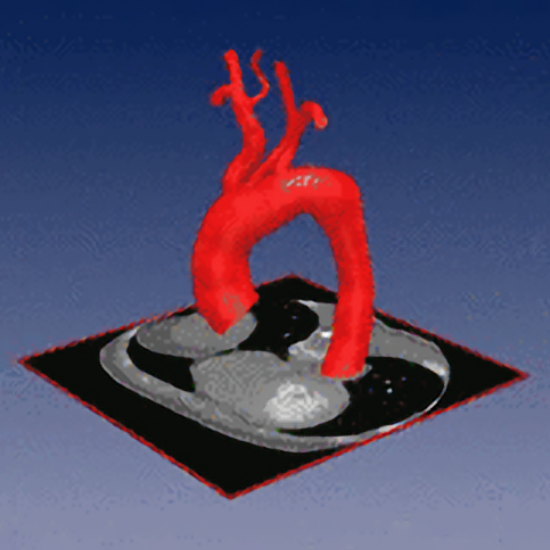

QuantVessel

Quantification of the Morphology of Human Vessels from 3D Tomographic Image Data (DFG Project)

Development of model-based approaches for accurate quantification of the 3D morphology of human blood vessels from 3D tomographic images (e.g., 3D CTA, 3D MRA). The approaches combine 3D cylindrical intensity models with incremental model fitting. The main application domain is the quantification of the aortic arch and its main bifurcating branches for improved operation planning using stent grafts.

3D Quantification of the Aortic Arch Morphology in 3D CTA Data for Endovascular Aortic Repair

Wörz S, von Tengg-Kobligk H, Henninger V, Rengier F, Schumacher H, Böckler D, Kauczor HU, and Rohr K

IEEE Transactions on Biomedical Engineering